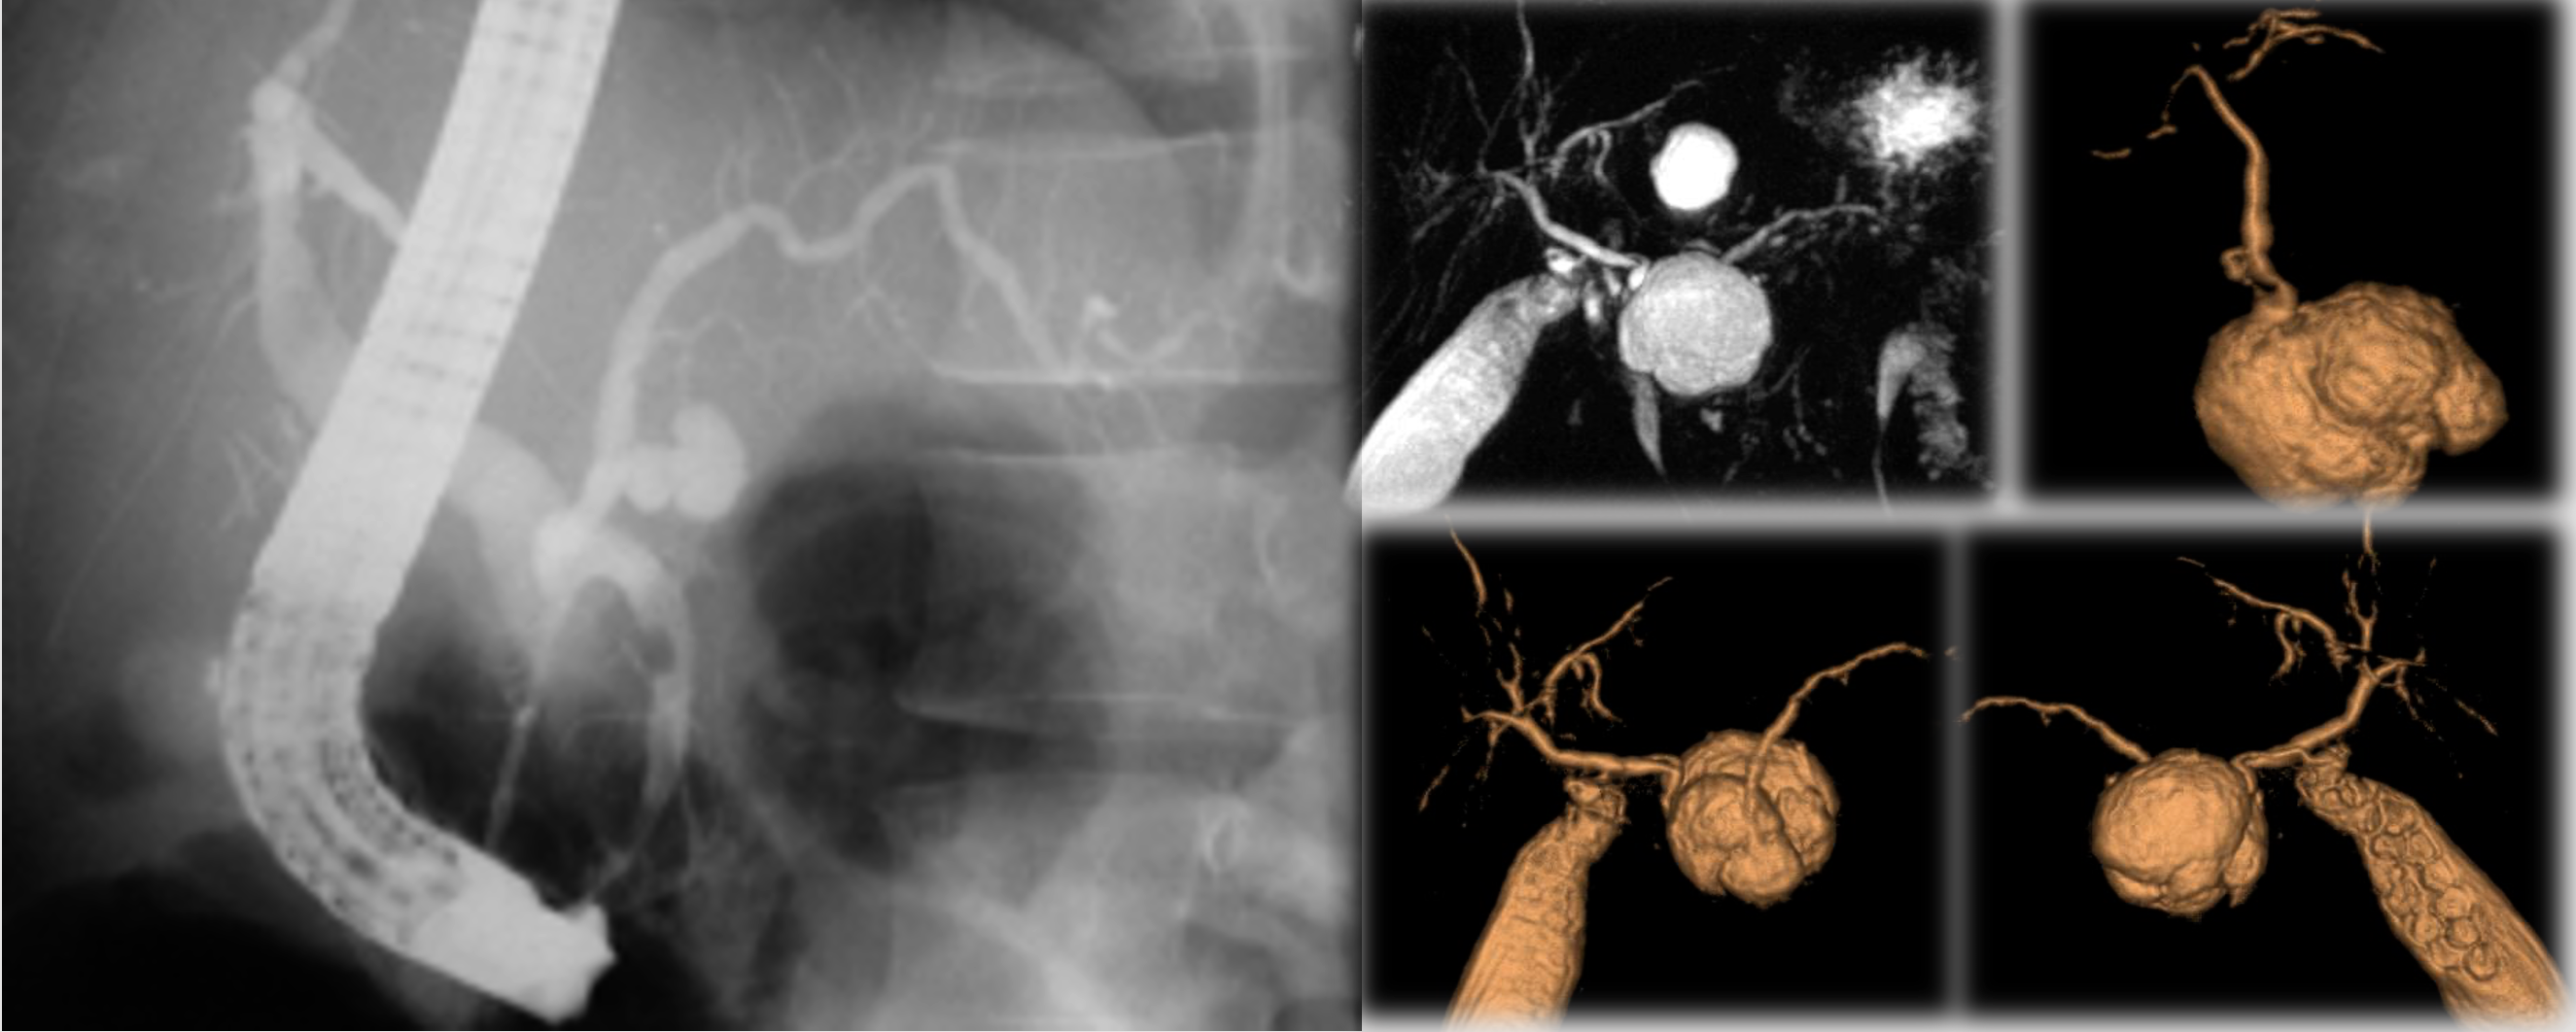

IPMT of the MPD

- Segmental or diffuse.

- Incidence M=F, Age: 6th decade.

- Radiologic features mimic chronic pancreatitis or chronic obstructive pancreatitis.

- ERCP remains the imaging modality of choice for diagnosis.